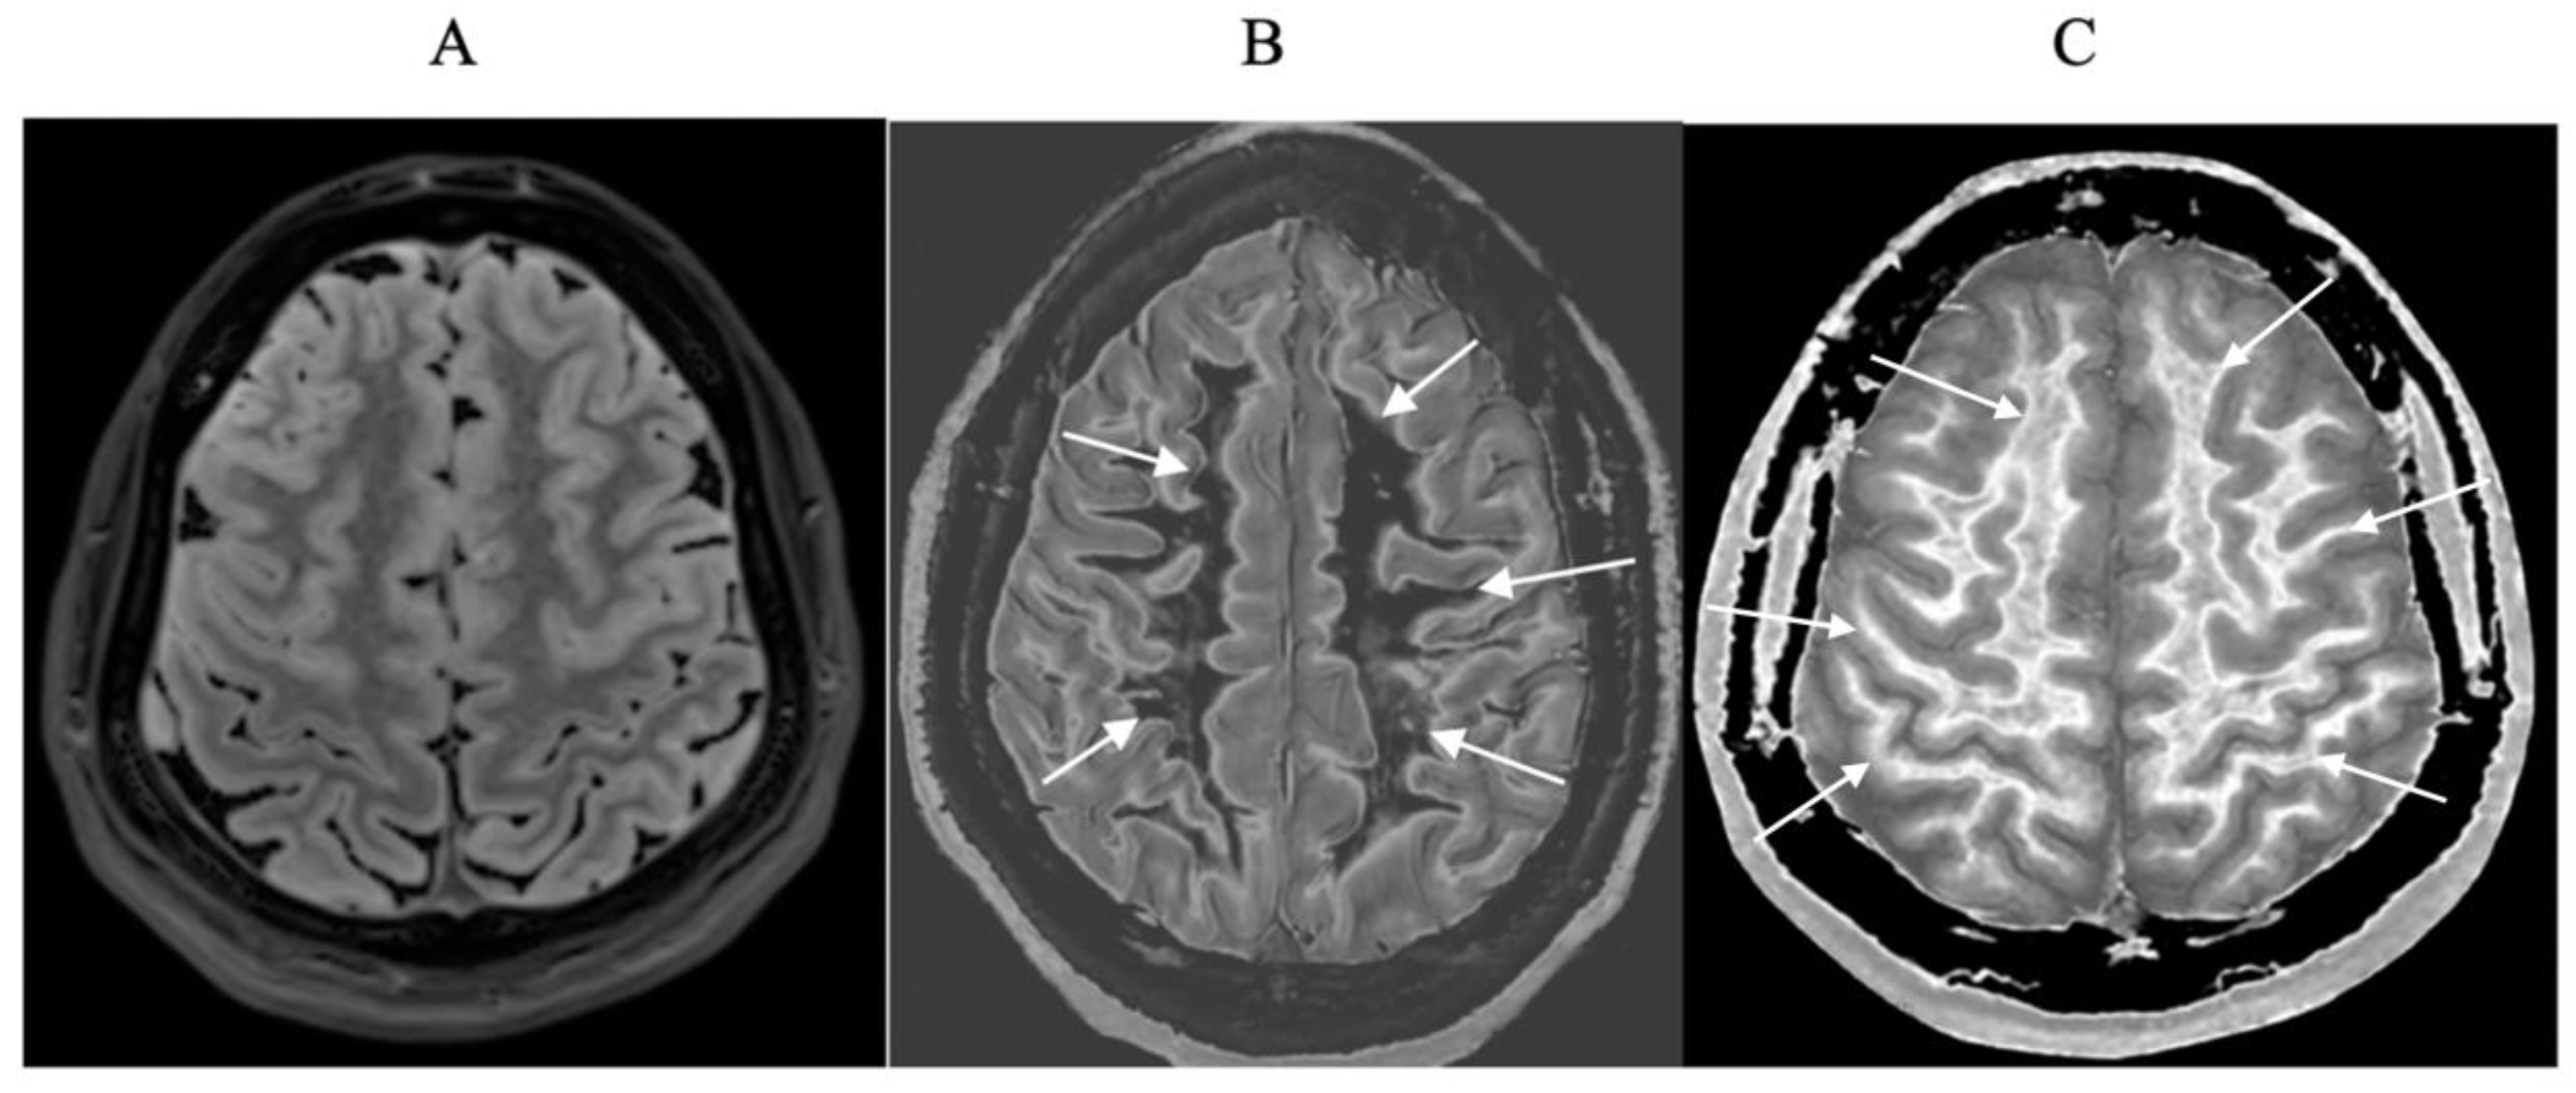

Small changes in T

1 may produce obvious abnormalities with the dSIR sequence as illustrated in a case of mild traumatic brain injury (mTBI) in an 24-year-old male patient (

Figure 1). No abnormality is seen on the T

2-FLAIR image in the patient (

Figure 1A). The dSIR sequence in a normal age matched control shows normal white matter in the cerebral hemispheres as low signal (dark) in

Figure 1B (arrows). The same dSIR sequence in the patient shows abnormal high signal in his entire white matter (

Figure 1C) (arrows). High signal (light) well defined boundaries are also seen between normal white and gray matter on the dSIR image in

Figure 1B. These are less obvious in

Figure 1C because of the high signal in the abnormal white matter.

Figure 1.

Positionally matched images of the brain in a 24-year-old male patient with mTBI (A and C) and a normal control (B). (A) is a T2-FLAIR image in the patient which shows no abnormality. (B) is a narrow mD dSIR (T1-BLAIR) image of the brain in the normal control. The white matter in the central region of this image has a normal low signal (dark) appearance (arrows). (C) is a narrow mD dSIR (T1-BLAIR) image performed in the patient with the same sequence as in the control. This image shows all the patient’s white matter with abnormal high signal (light) (arrows) rather than the normal low signal (dark) appearance in the control (arrows) (B). There is a night and day difference in signal between normal and abnormal white matter in (B) and (C). High signal boundaries are seen between normal white matter and normal gray matter in (B). These are less obvious in (C) because of the high signal in the abnormal white matter.